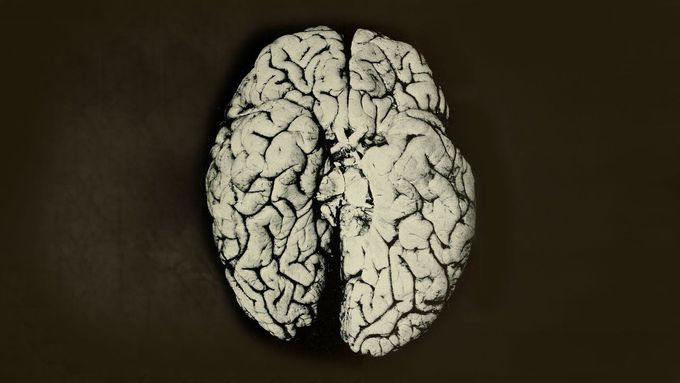

A Scientist Spilled 2 Drops Organic Mercury On Her Hand. This Is What Happened To Her Brain.

This is based on the true story of Professor KW. Music by Lifeformed ► https://lifeformed.bandcamp.com/ 3D T2 Brain MRI Imaging ► https://www.youtube.com/watch?v=IIX78qGYeAo Talk To The Hand Sample ► https://www.youtube.com/watch?v=8aQ9Wecrnj0 A Febrile Toddler Played With His Cat. This Is What Happened To His Brain ► https://www.youtube.com/watch?v=DuGsc6FkyTY A Boy Ate 25 Laxative Brownies In 1 Hour. This Is What Happened To His Kidneys ► https://www.youtube.com/watch?v=TMy0vJfKvzI Medicine ► https://www.youtube.com/watch?v=J3HivpHP-5I&list=PL26HeTCO57qcMQB6CrU6QRzEi9tt9l1FI I hold no responsibility over what you do with your body after watching any of my videos. You should not recreate any of the presented situations. The images shown here are dramatizations of the actual story which has been documented in writing. These videos are not and are not intended to be medical advice. I do not give individualized medical advice over the internet, see your physician for that. I am a licensed provider trained and based in the United States with no conflicts of interest in presenting this case, or any other case published before this one. #laboratory #lab #chemistry #science #scientist #hospital #patient #treatment #hospital #physician #pharmacist #nurse #metal #heavymetal #medical #medicine #brain #eye #doctor